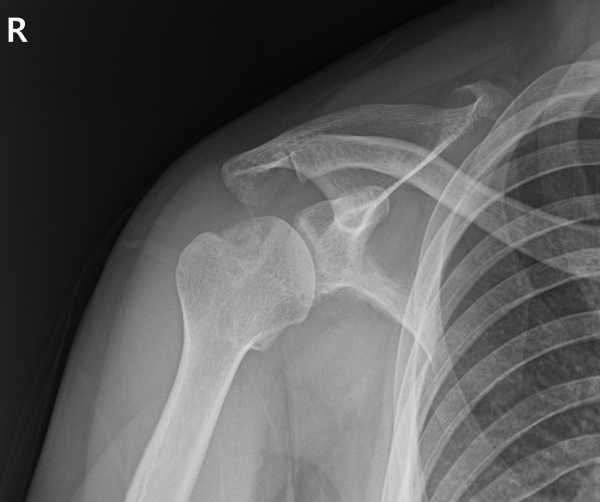

재파열된 전하방 관절와순파열(Bankart) 병변(Recurrent Bankart lesion-재발성 전하방 관절와순파열)

매우 깊고 넓은 상완골두 후외측 골결손(Hill-Sachs) 결손(huge Hill-Sachs lesion-거대 상완골두 후외측 골결손)

상완골두 변형 및 결손

부분층 회전근개 파열

이 정도면 단순한 재탈구 수준을 넘어, 어깨 관절의 안정성이 거의 상실된 상태였습니다.

2. 일반적 수술로는 회복이 어렵다는 판단

상완골두 후외측 골결손(Hill-Sachs) 병변의 크기가 매우 컸기 때문에 단순 봉합이나 기존 방식의 수술만으로는

관절의 회전 중심을 되찾기 어려웠습니다.